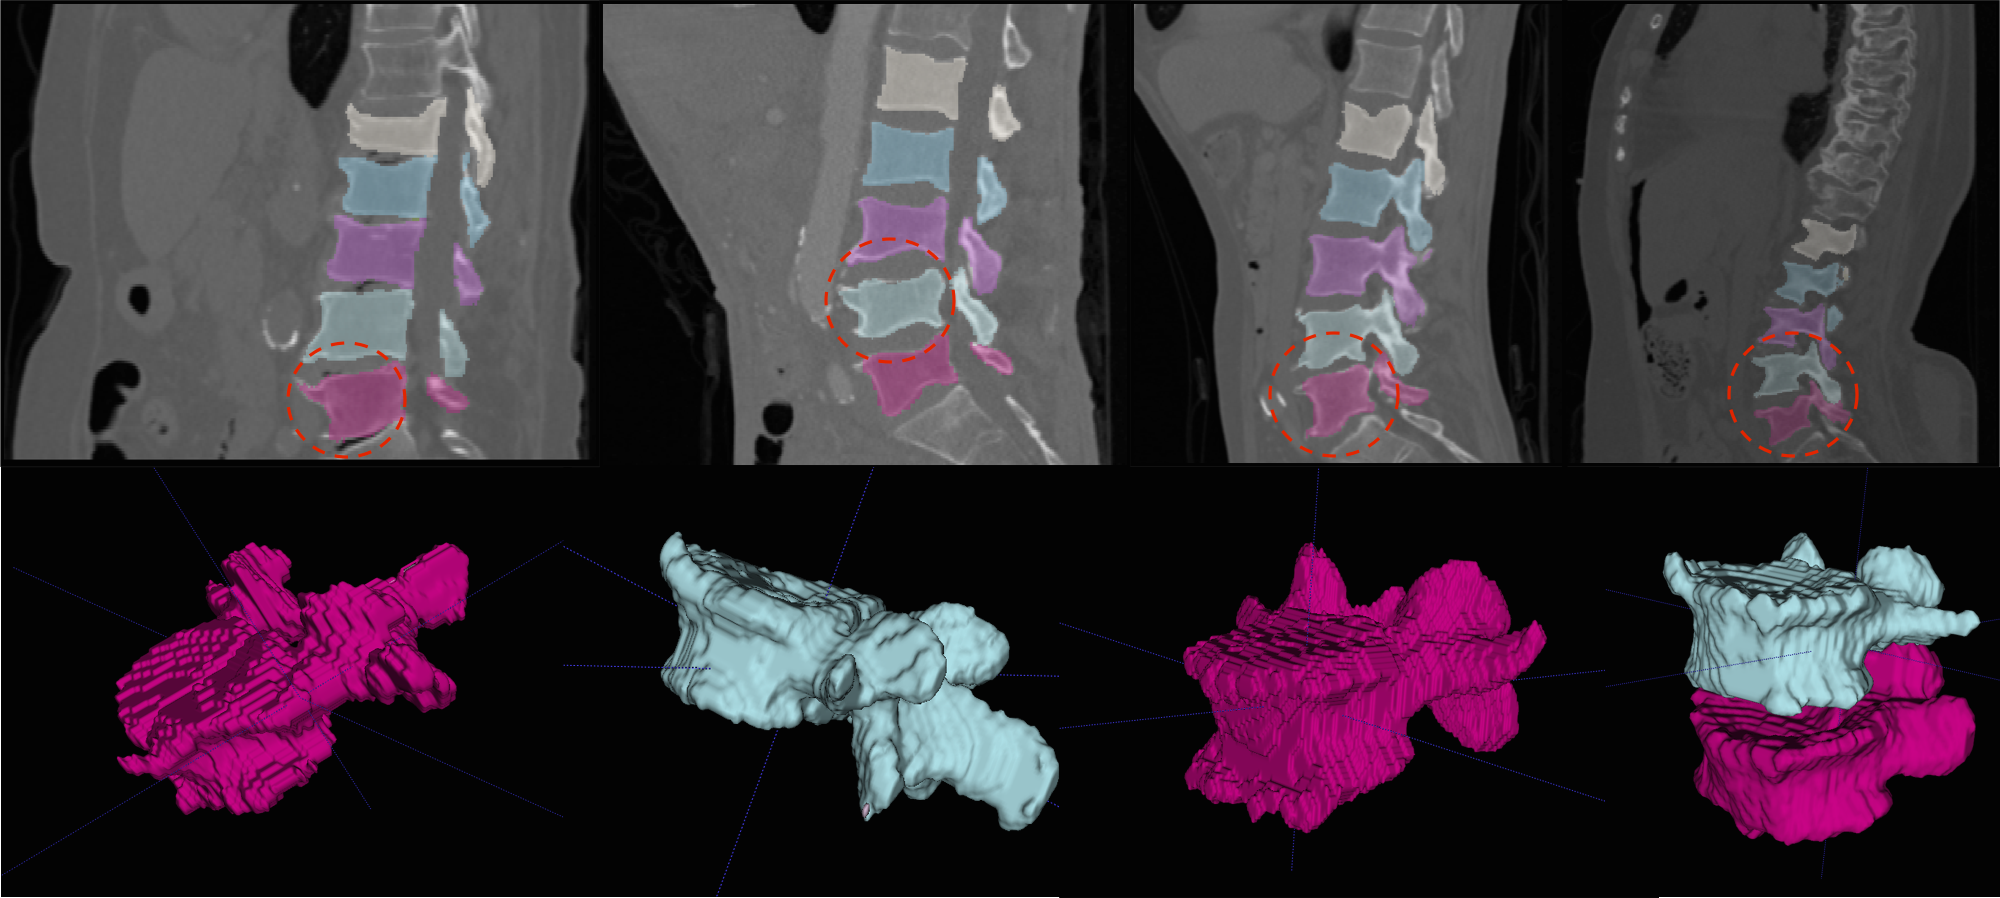

In general, both the stages in our pipeline work remarkably well as per the quantitative results in tables 1 and 2. We obtain a near perfect localisation of 1.0 for almost every case, and a mean Dice score of 92%. In addition to this, the prime motivation of our approach is to successfully segment the deformed spines where the model-based approaches fail. This can be observed visually in figure 4. Four test cases as shown highlighting the highly deformed spine and vertebrae. Observe that our algorithm successfully segments these cases in spite of the severe deformations.

We present more results of multi-class segmentation on the test set of xVertSeg (figure 5) in addition to the results in figure 4, thereby emphasising the robustness of our approach. We also present a few aberrant segmentations analysing which could further improve our approach.